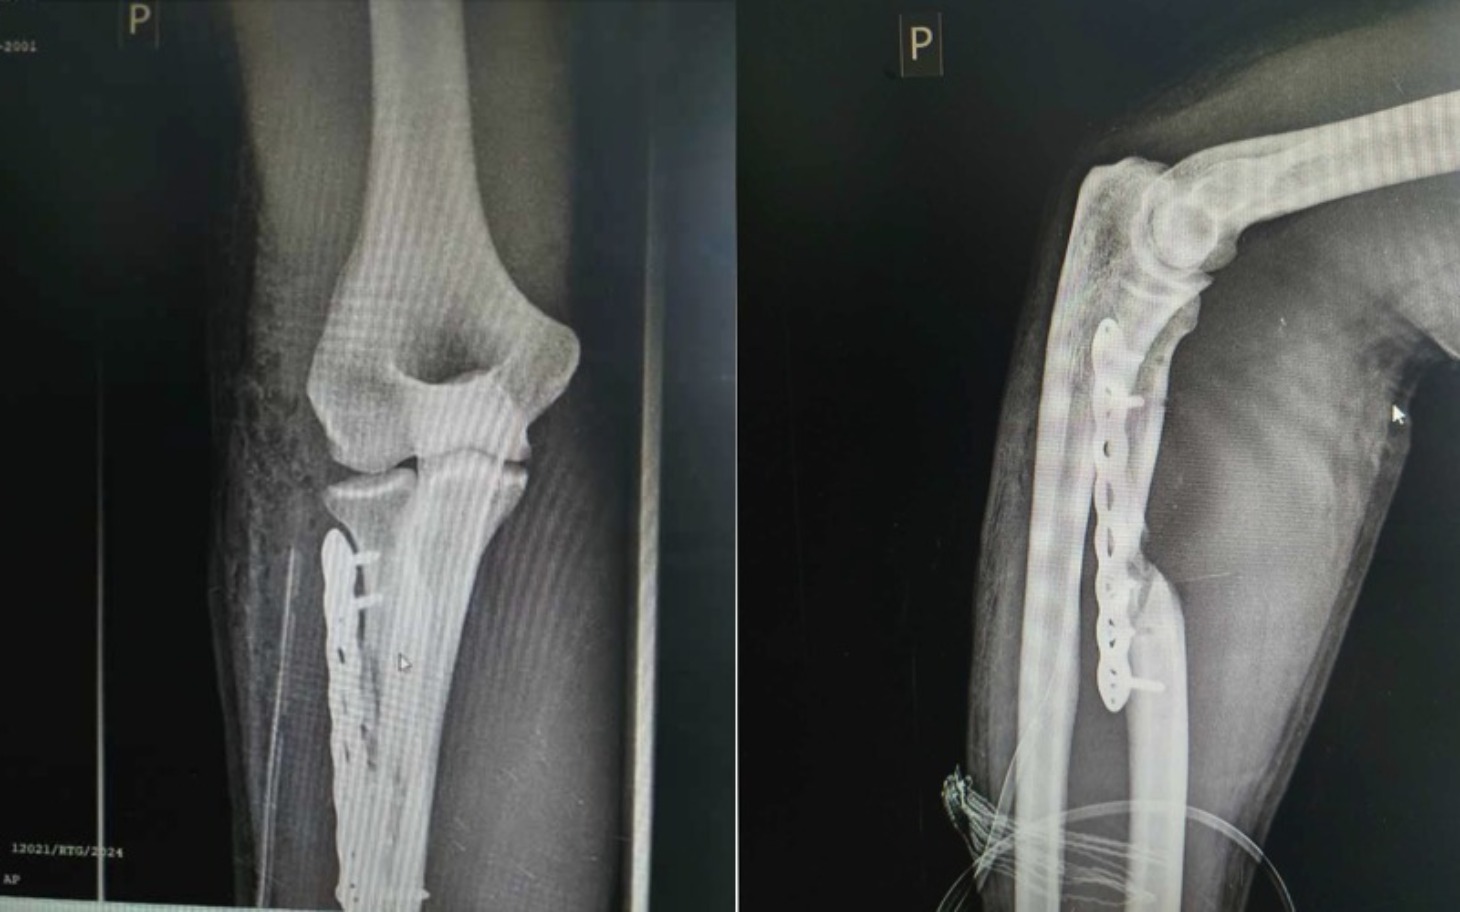

Zamiast ratunku – "oskalpowanie". Pierwsza operacja w ZCO w Dąbrowie Górniczej była początkiem drogi przez piekło. Obudziłem się z bólem, którego nie da się opisać, i dłonią, która była bezwładna. Kiedy sam, na własną rękę, wyprosiłem zdjęcie RTG, przeżyłem szok: kości krzywo ułożone osiowo, śruby wyrwane, płyta stabilizująca wisząca bez stabilizacji, porażenie nerwu powodujące całkowite zwiotczenie dłoni, uszkodzone ukrwienie. Ortopedzi w innym szpitalu nie przebierali w słowach: zostałem "oskalpowany", a moja ręka wyglądała jak po wybuchu bomby. Lekarz operujący wyjmował śruby palcami.. To wszystko spowodowało, że moja kość zamiast się zrastać przez kolejne miesiące tylko obumierała..

Ponad rok w matni bólu i upokorzenia. Ta jedna „zwykła” operacja spowodowała, że moja kość stale obumierała powodując 3 cm ubytku w kości co widać na RTG przedstawiającym rękę na luty 2025 już po dwóch operacjach (zepsuta w ZCO DG i naprawiająca w Szpitalu Miejskim w Sosnowcu. Do 29.01.2026, przez ostatnie półtora roku przeszedłem poważne 3 operacje stabilizacji kości, w tym jedną z przeszczepem kości z biodra do ręki oraz 1 zabieg biopsyjny - dodatkowe wiercenie drugiego biodra i bolesne ostrzykiwanie szpikiem biopsyjnym, serii ostrzyknięć komórkami wzrostowymi, niekończącą się rehabilitację i zabiegi, przy których ból do prowadzał do utraty przytomności. Co tydzień jestem podpinany pod bardzo nieprzyjemny prąd aby naprawić porażony nerw. Miałem być oparciem dla bliskich, a stałem się człowiekiem, którego partnerka musi myć gąbką na stołku, bo sam nie jest wstanie ustać z bólu, oraz pomagać mi w codziennej egzystencji. To upodlenie, którego nie życzę nikomu, zwłaszcza gdy masz całe życie przed sobą. Miałem być oparciem a stałem się ciężarem, którego sam nie mogę unieść..

Ostatni dzwonek. Mimo mojej walki, diagnoza ze stycznia 2026 roku zwaliła mnie z nóg: staw rzekomy, brak zrostu. Lokalni lekarze sugerują skrócenie ręki o 3 cm i "nauczenie się życia z kalectwem". To również powoduje potencjalną szansę na nie zrost kostny. Jestem po 3 operacjach w tym jednej z przeszczepem kości z biodra i 1 zabiegu wiercenia biodra i ostrzyknięciu szpikiem kostnym. Na horyzoncie kolejna operacja a mam obecnie dopiero 24 lata..